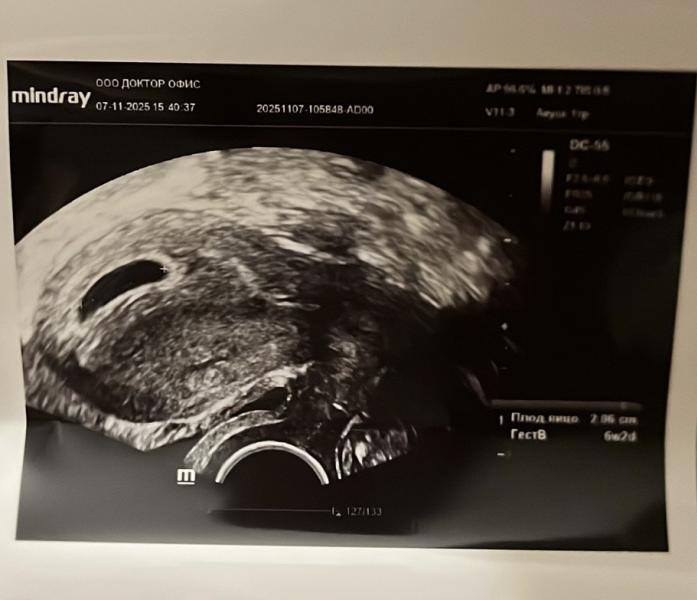

Беременность подтвердилась,сердце наполнилось таким счастьем, что словами не передать. У меня будут погодки!!!!